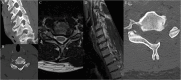

Figures